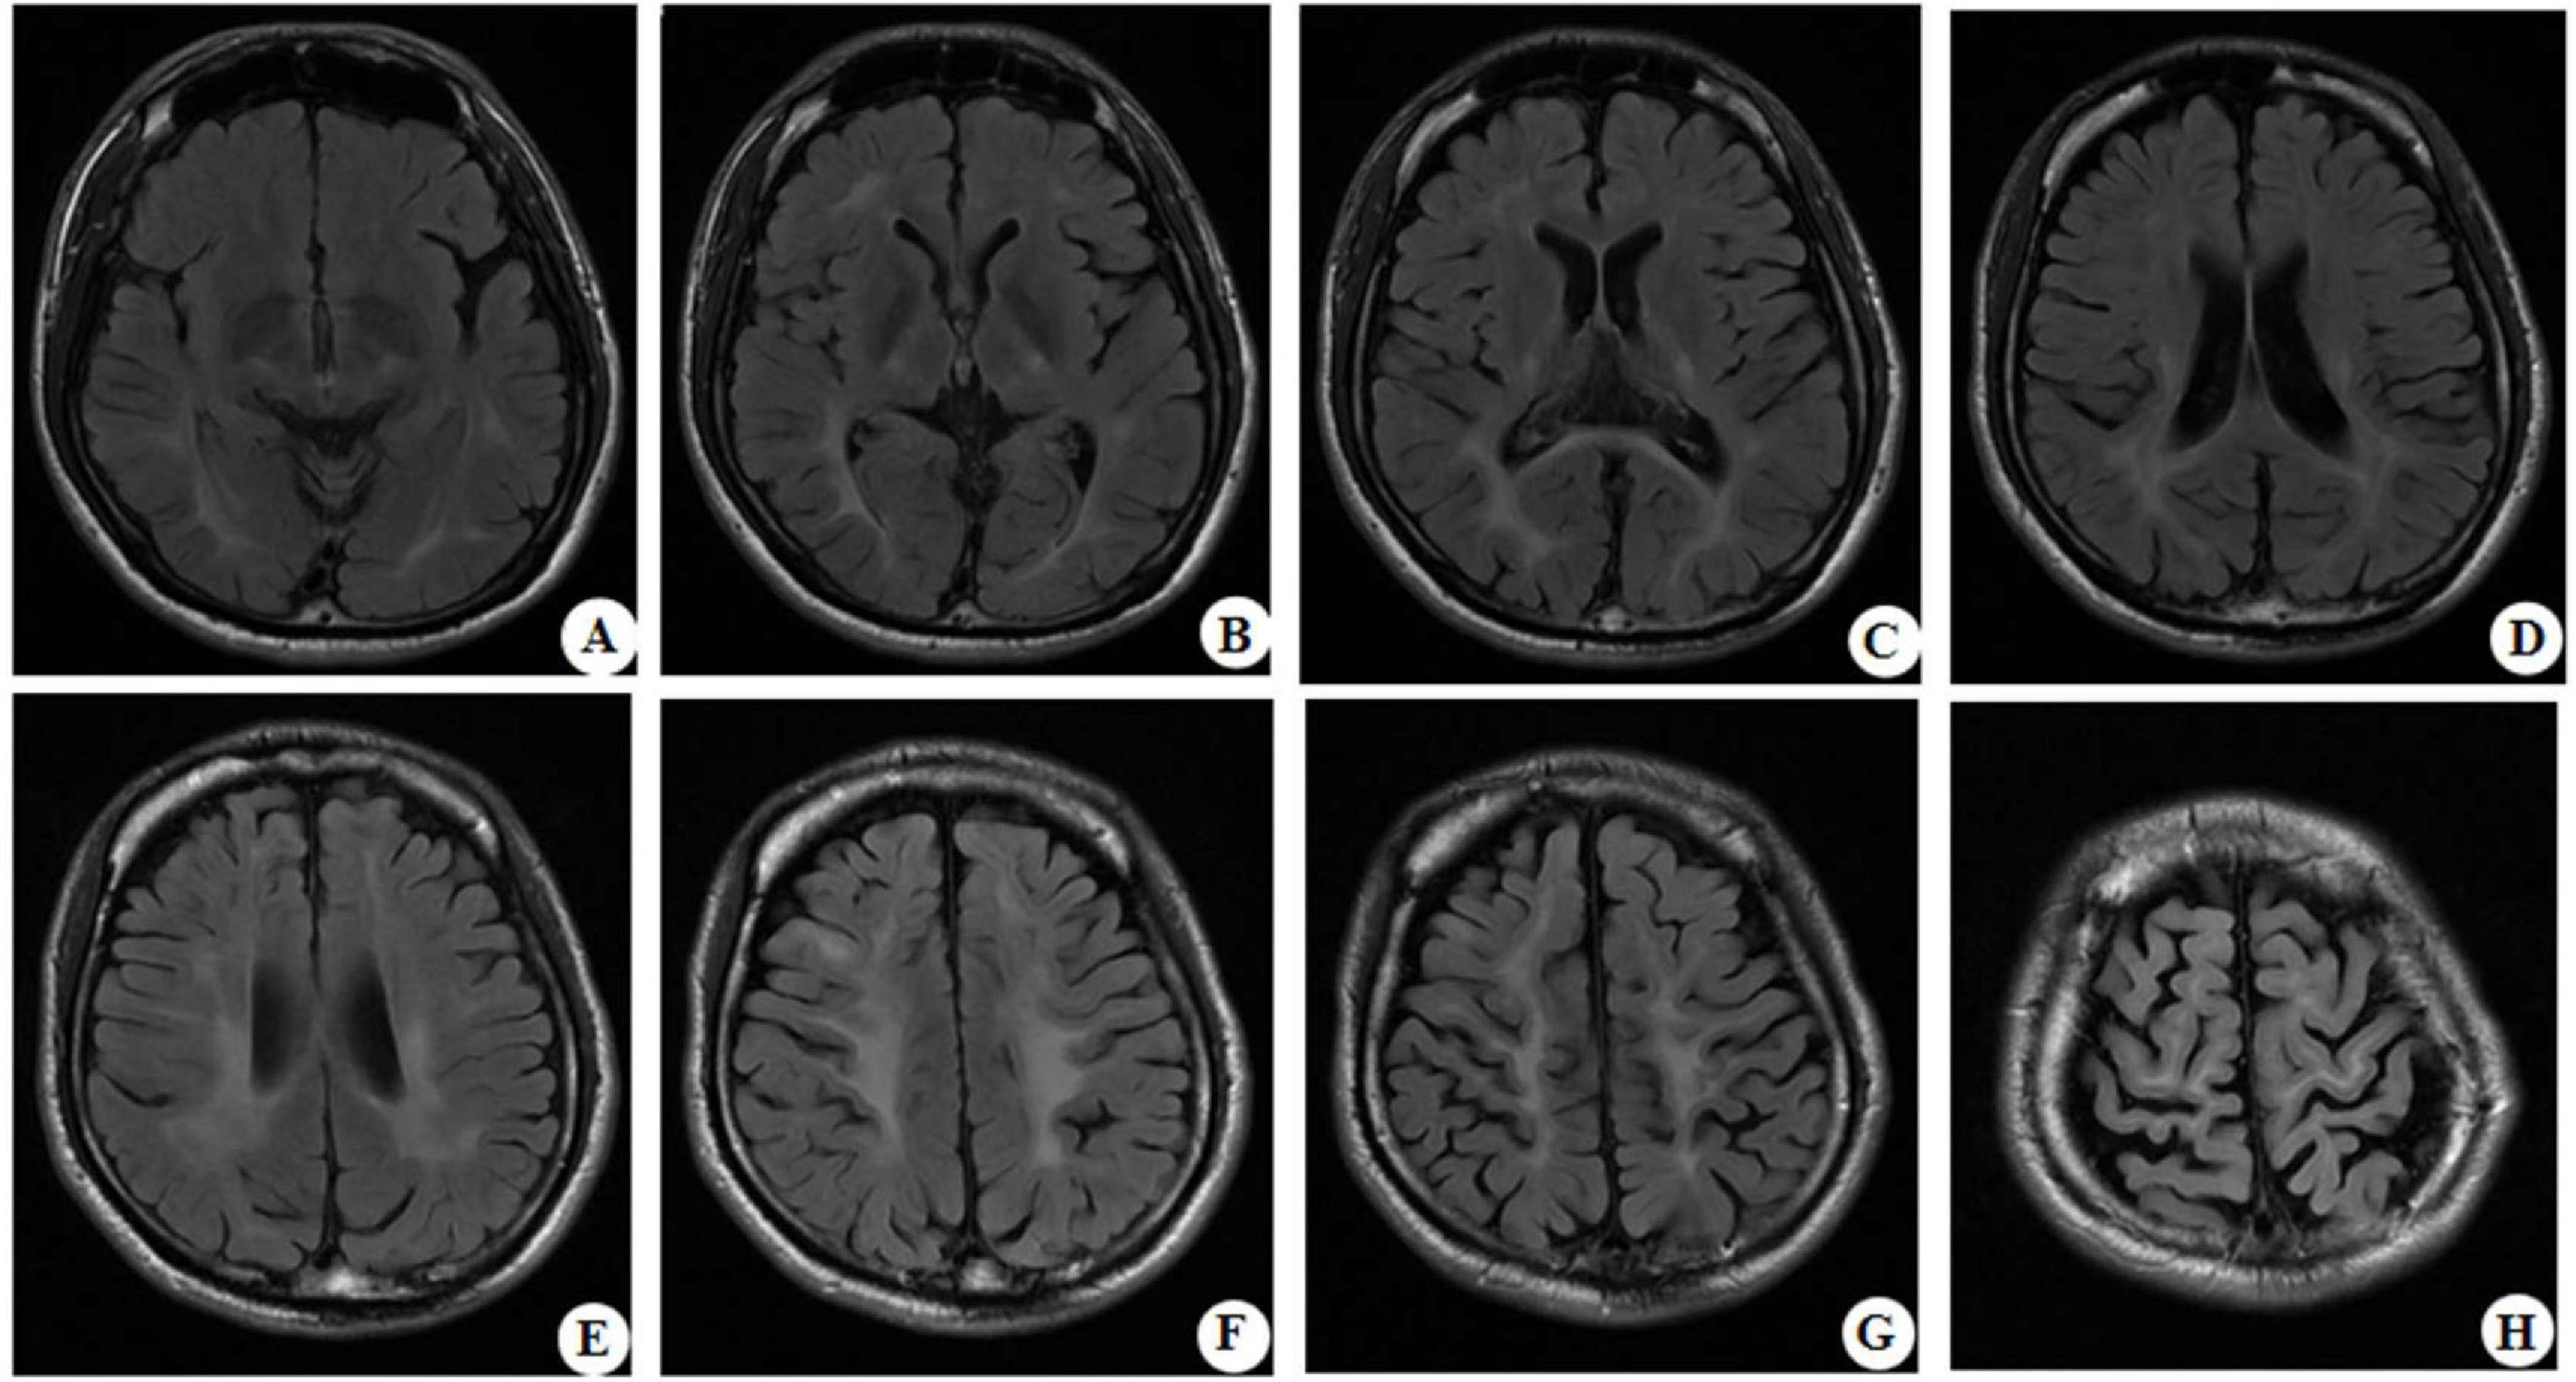

At the age of 16 years, his brain MRI showed bilateral high-signal abnormalities in the periventricular white matter and corticospinal tracts, along with a lesion in the right frontal subcortical region (Figure 2A). And the age of 26 detected symmetrical lesions in the bilateral corticospinal tracts, optic radiations, splenium of the corpus callosum, bilateral corona radiata, and the centrum semiovale (pre- and postcentral gyri) white matter, along with newly observed diffuse cerebral atrophy (Figure 2B). Subsequent MRIs conducted in 28 years old demonstrated progressive involvement of the frontal, parietal, temporal, and occipital lobes (Figures 3A–H). Physical examination revealed pes cavus (high-arched feet). While the patient denied marked sensory deficits, the neuroelectrophysiological examination revealed peripheral nerve damage, mainly demyelinating changes, and bilateral abnormal upper and lower limb sensory evoked potentials (Figure 4). So far, he has not exhibited significant visual decline. Ophthalmologic evaluation at Zhongshan Ophthalmic Center confirmed corrected visual acuity of 1.0 bilaterally, normal visual fields on perimetry, and unremarkable fundus examination, excluding optic nerve involvement. Cognitive assessment using the Mini-Mental State Examination (MMSE) yielded a score of 28/30 (adjusted for junior high education level), indicating preserved cognitive function. Laboratory test results were normal, including the amino acid and acylcarnitine spectrum analysis, content of very long chain fatty acids, adrenocorticotrophic hormone, cortisol, and creatine kinase.

FIGURE 3

MRI brain scans in a grid layout labeled A to H. Each scan shows cross-sectional images with varying levels of detail in brain structures and tissues, highlighting differences in density and texture.

Figure 3. Representative brain MRI at the age of 28 years (T2 FLAIR, axial planes). Symmetrical abnormal signals are observed in the subcortical white matter of the bilateral frontal, temporal, parietal, and occipital lobes, the bilateral frontal and parietal cortex, the bilateral posterior limbs of the internal capsules, the bilateral corona radiata, the bilateral centrum semiovale, and the splenium of the corpus callosum.

Neuroimaging of KD typically shows symmetrical lesions in the periventricular white matter, corticospinal tracts, and optic radiations (Cousyn et al., 2019; Muthusamy et al., 2019). In the patient of this study, MRI revealed not only characteristic white matter abnormalities but also initial right frontal subcortical signal abnormalities, progressing to involve bilateral fronto-parietal cortex and cortical atrophy as the disease developed. Notably, Ketata et al. described parieto-occipital lesions in KD, linking to psychosine-mediated demyelination and neuroinflammation (Ketata and Ellouz, 2024). The fronto-subcortical findings of this study may share similar pathogenesis, reflecting regional vulnerability to psychosine toxicity. It is possible that KD had a broader spectrum of radiological patterns, underscoring the need for further studies to clarify its pathophysiology, clinical significance, and potential prognostic implications.

The cortical or subcortical gray matter changes observed in the presented patients might predispose to epileptogenesis, which may be the possible explanation of the observed initial symptom of GTCS. This finding expands the imaging spectrum of KD, suggesting that clinicians should consider the differential diagnosis of KD for adult epilepsy patients with frontal lobe abnormalities. Notably, the patient later developed spastic paraparesis, high-arched feet, and peripheral nerve involvement, paralleling the typical adult-onset KD phenotypes. The unique compound heterozygous variants in this patient may be associated with the atypical clinical course. As the disease progresses, the patient gradually shows typical adult-onset KD symptoms, suggesting that despite the difference in the genetic background, there are still certain commonalities in the disease development process, although the initial stage and the progression rate may vary. However, this hypothesis requires further verification through functional studies and the accumulation of more cases.